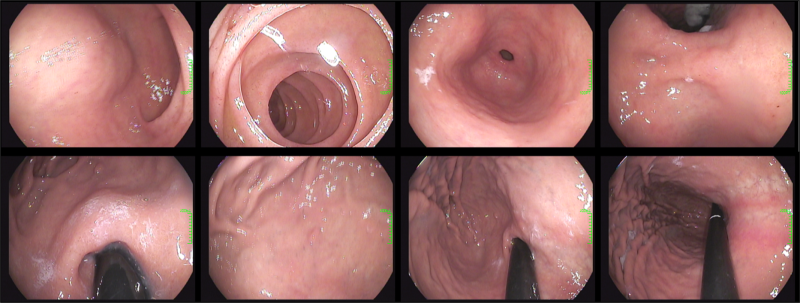

Naver Reservation: You can make an appointment for an endoscopy at Naver Reservation at the rumored Internal Medicine/Medical Examination Center in Fengam-dong, the stomach/colorectal endoscope. In addition to sleeping/non-sleeping gastric endoscope sleeping/non-sleeping colonoscopy liquid bindings, tablet bindings can be selected for comfortable and accurate examination with CO2 gas that makes your stomach comfortable.m.booking.naver.com